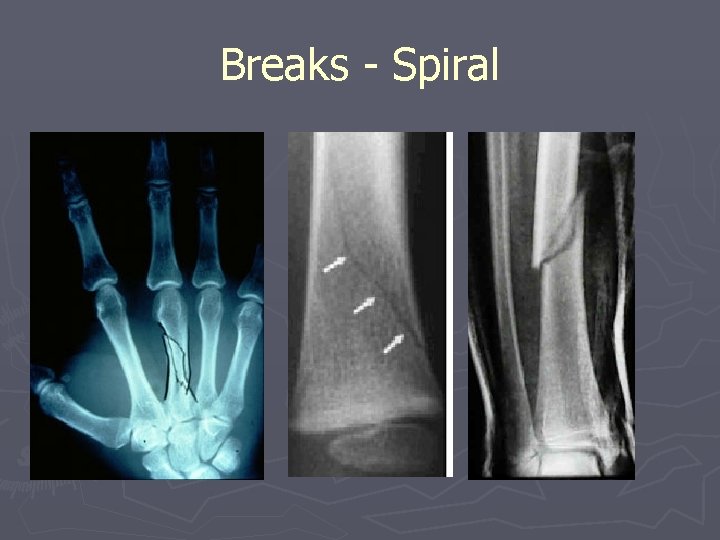

Problems with Skeletal System Breaks ► Complete/Incomplete (Greenstick) ► Displaced ► Simple/Compound (breaks skin) ► Impacted or Comminuted ► Spiral ► Hairline

Breaks - Spiral